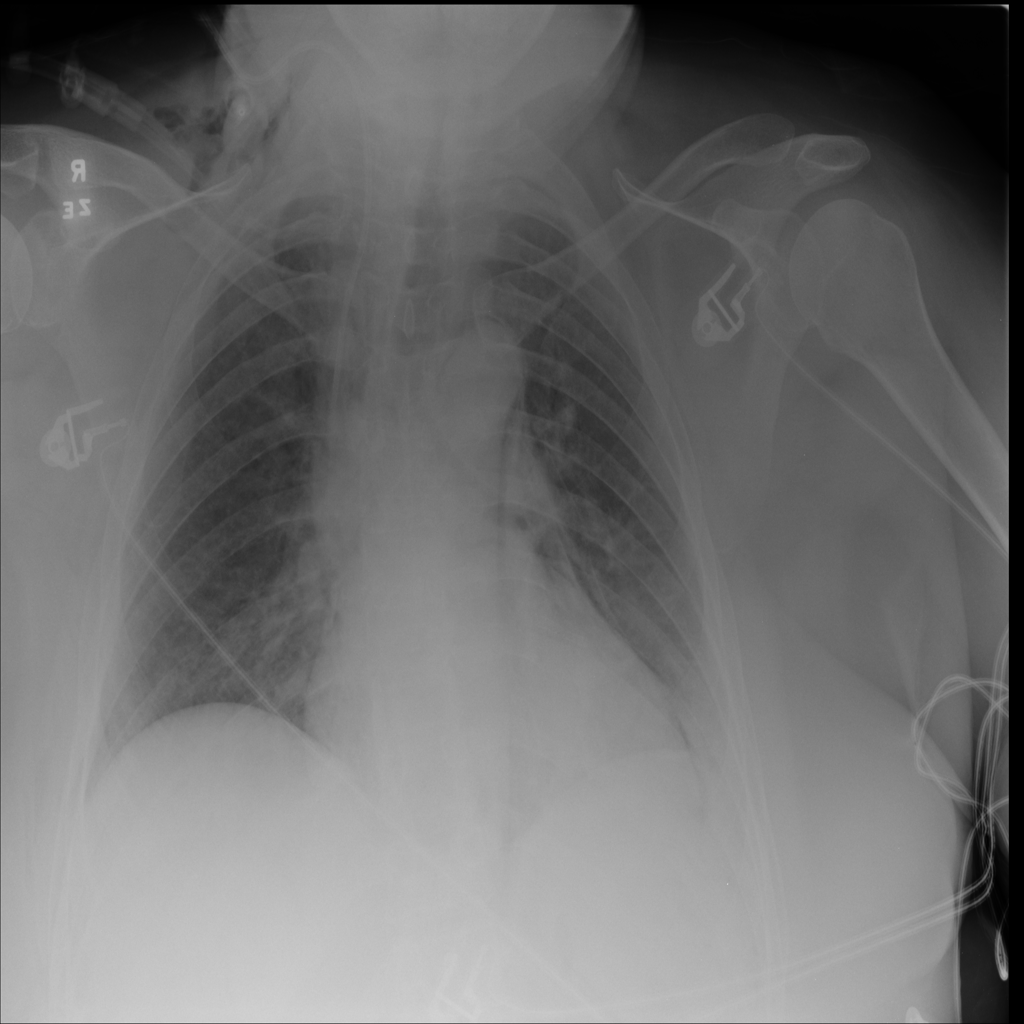

PAT-C255 · IMG-000Emphysema

PAT-C255 · IMG-000

PA